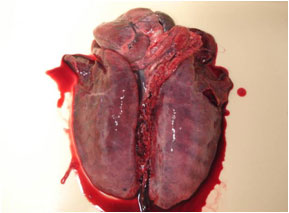

剖検:

- (1)肝の腫脹と小白色壊死斑の散在

- (2)脾腫